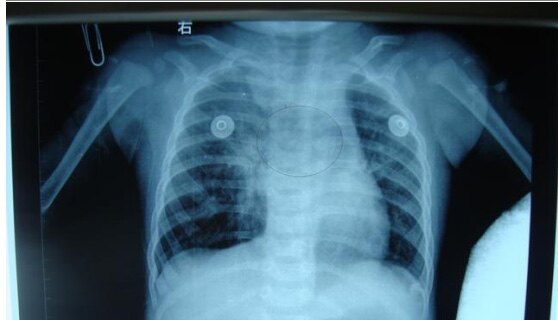

纵隔疝

纵隔疝的临床表现与诊治方法

每日一例412纵隔疝